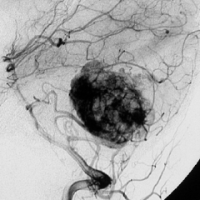

- 椎骨動脈撮影では,著明な腫瘍濃染像(血管がいっぱい)がみられて確定診断が可能です

真偽のほどは解りませんが頭の中で血液が流れる音がするというのが主訴です。その後に軽度の歩行失調と構語障害が出て発見されました。この程度のものでもAVMと同じように血管雑音を自覚することがあるのかもしれません。画像をよく見ると右の小脳扁桃のもので,延髄はただ圧迫されているだけです。血管芽腫はエリスロポエチンを産生して多血症になることがあるのですが,この患者さんは16.6 MIU/mlで正常値でした。

右のPICAが主たるfeeding arteryです。でもPICAのretromedullary segmentからshort feedersが流入していますから,油断をすると延髄背側障害という厳しい手術合併症を生じる可能性は十分あります。この腫瘍は正中後頭下開頭で全摘出できましたし,神経脱落症状を残していません。難易度は中等度のものです。